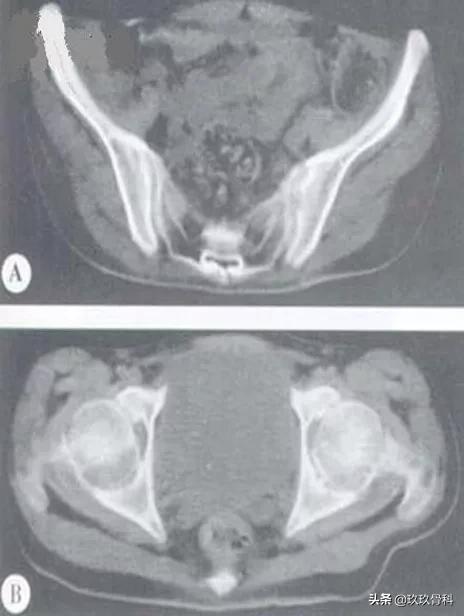

强直性脊柱炎(Ⅱ级)

图注:A.CT示双侧骶髂关节模糊,骨侵蚀破坏,右侧明显,关节间隙无改变。B. CT示双侧髋关节间隙变窄,关节骨面质破坏呈锯齿状,以髋臼明显。